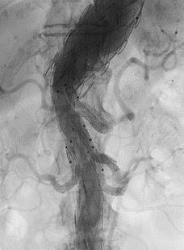

Komplexes Aneurysma der Bauchschlagader: mit einer über die Leistenregion minimal invasiv eingebrachten Stentgraft – Prothese versorgt, zusätzliche Schienung lebenswichtiger Organarterien (Nieren, Darm, Leber etc.) – sog. 4-fach gebranchte Prothese

Dabei handelt es sich zumeist um modulare Prothesensysteme. Hierdurch wird der Gefäßstrom durch die Prothese geleitet und somit das Aneurysma ausgeschaltet.

Minimalinvasive Eingriffe haben den Vorteil einer erniedrigten peri/postoperativen Mortalität, einer deutlich verkürzten Liegedauer und benötigen so gut wie keine rehabilitierenden Maßnahmen, allerdings müssen die Aortenprothesen jährlich mittels CT-Angiographie kontrolliert werden um etwaige Komplikationen (weiteres Aneurysmawachstum, Materialdefekte) frühzeitig zu erkennen und in weiterer Folge auch beheben zu können.